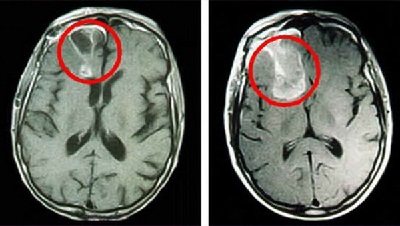

Наилучшими способами объективного выявления опухоли полушарий мозга признаны методы нейровизуализации: КТ и МРТ головного мозга. Они позволяют определить точную локализацию опухоли полушарий мозга и дифференцировать ее от внутримозговой гематомы, кисты при сирингомиелии, абсцесса головного мозга, рассеянного склероза, эпилепсии. Однако поставить достоверный диагноз и верифицировать опухоли полушарий мозга позволяет лишь гистологическое исследование. Оно может проводится с образцами мозговой ткани, полученными в ходе стереотаксической биопсии или интраоперационно.

Для адекватной оценки глиомы головного мозга пациента направляют на магниторезонансную томографию. Именно этот вид диагностики позволяет точным образом в трехмерном изображении определить местоположение опухоли, ее объем и зону поражения.

Магнитно-резонансная томография (мрт) при глиобластоме

МРТ позволяет с высокой степенью уверенности говорить о диагнозе мультиформной глиобластомы и широко используется для определения местоположения и размера опухолей мозга. Фактически, этот метод имеет наивысшую степень достоверности среди других лучевых методов. Некоторые другие процессы, в основном объёмные образования с геморрагическим компонентом, могут имитировать мультиформную глиобластому на МРТ, включая абсцессы мозга и инфаркты. В случае неясной или спорной МРТ-картины может быть полезной экспертная оценка МРТ специализированными радиологами.

Как выглядит глиобластома на МРТ? Как правило, образование на томограммах представляет собой зону, имеющую в основном пониженный сигнал на Т1-взвешенных изображниях и повышенный сигнал на Т2- взвешенных изображениях. Могут присутствовать внутренние кистозные участки, участки потери сигнала, обусловленные крупными сосудами, внутренние зоны повышенной интенсивности сигнала на Т1-ВИ (геморрагические очаги), новообразованные сосуды, очаги некроза, обширный перитуморозный вазогенный отеком и значительный масс-эффект. Также может выявляться неравномерное, но интенсивное накопление контрастного вещества на основе гадолиния (та же картина наблюдается на КТ после введения йодсодержащего контраста), как в основной опухоли, так и в метастатических очагах, характерных для МФГ. МРТ более чувствительна к этим изменениям, чем КТ.